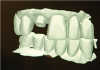

Fig. 32 through Fig. 34 An implant restoration can be designed virtually on CAD software with no analog impression or model. The software has the option of designing a screw-retained crown or splitting the file and designing a custom abutment and crown.